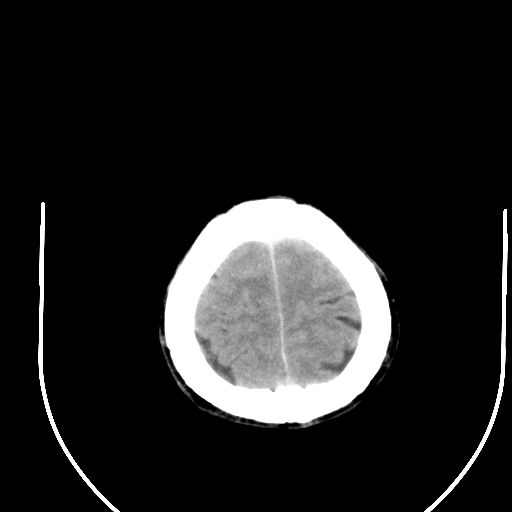

右侧基底节区脑出血并破溃入脑室。

1右侧基底节脑出血伴脑干出血并破入脑室系统脑疝形成2梗阻性脑积水

1)右侧基底节脑出血伴脑干出血并破入脑室系统。2)大脑镰下疝。3)梗阻性脑积水。

1、右侧基底节脑出血伴脑干出血并破入脑室系统。

2、大脑镰下疝。

3、梗阻性脑积水。